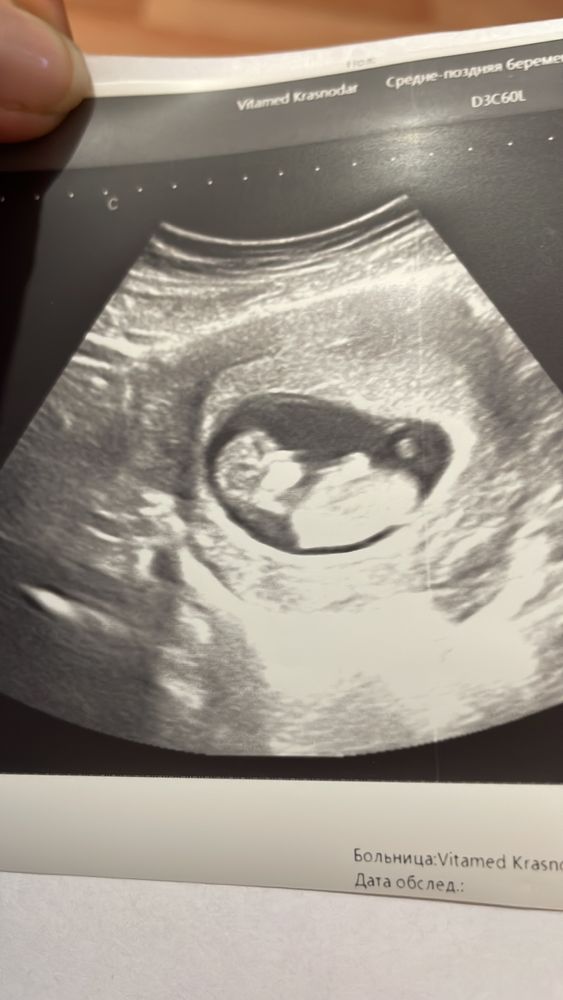

ЗеЛеНоГлАзКа в Благополучная беременность год УЗИ 11 и 4 пол ребёнка Пол малыша Ничего не могу разглядеть по фото! Может у кого глаз наметан Посмотрите еще 20 записей на эту тему Лучший ответ Алина Это фото не того качества,чтобы разглядеть 17.10.2024 Ответить ЗеЛеНоГлАзКа Алина, к сожалению , все что дали ☺️ 17.10.2024 Ответить Отменить Ответить Святая инквизиция Да рано вам еще) 18.10.2024 Ответить Таролог Тут не видно, к сожалению 17.10.2024 Ответить Dasha Мне кажется девочка) 18.10.2024 Ответить За восходом Качество плохое и положение, мальчик, возможно. 17.10.2024 Ответить Надя А врач кого предположил? 17.10.2024 Ответить ViksikKash Девочка думаю 17.10.2024 Ответить Это то что я думаю?🤔 Определение Пола малыша👼 Чаты Беременных Выберите чат: Январята-2026 Февралята-2026 Мартята-2026 Апрелята-2026 Майчата-2026 Июнята-2026 Июлята-2026 Августята-2026